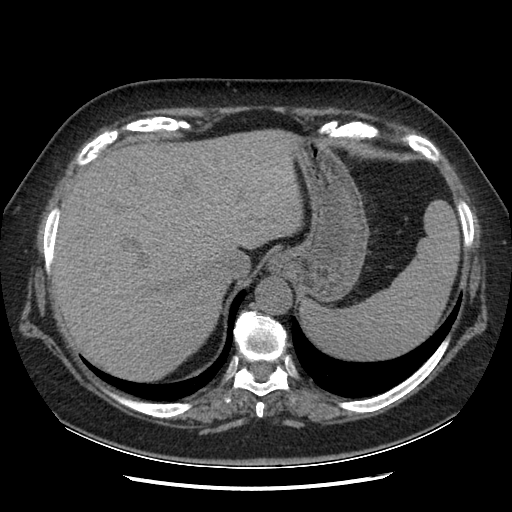

Generated VENOUS CT scan (A→B translation)

Full window (WL 1023.5, WW 4095 β†’ Low βˆ’1024, High +3071)